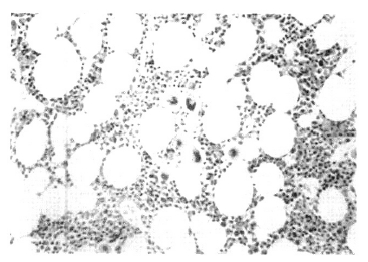

A 37-year-old woman was admitted to our hospital due to gum bleeding and petechiae in both lower extremities for three days. She had a known diagnosis of AITP and had undergone a splenectomy 11 years ago. She denied taking any medications prior to this hospitalization. On admission, her temperature was 36.6°C and her blood pressure was 110/70 mmHg. The physical examination was unremarkable except for the oozing of blood in oral cavity and a diffuse petechiae in both lower extremities. A splenectomy scar was present in her abdomen. The WBC was 7,200/mm3, hemoglobin was 12.4 g/dL, and platelet count was 3,000/mm3. The serum electrolytes and liver chemistry were within normal limits. Serum urea nitrogen and creatinine were normal. A routine urine analysis showed the presence of microscopic hematuria. The coagulation profile was all within the normal limits. Daily prednisolone and intravenous immunoglobulin (IVIG) were started. A spleen scan obtained after the intravenous injection of technetium-99m-labeled denatured RBC revealed a focal uptake in the posterior aspect of the left upper quadrant, and these findings are consistent with the presence of an accessory spleen (Figure 1). A computed tomographic (CT) scan of the abdomen revealed a 2×2 cm sized soft tissue lesion on the left sub-diaphragmatic area (Figure 2). On the 22nd hospital day, an accessory splenectomy was performed and the operation proceeded without complication. A dark brown mass was obtained and the pathologic finding was splenic tissue (Figure 3). The postoperatively platelet count soon increased to 71,000/mm3 and the patient was discharged. Two months after the accessory splenectomy, her platelet count dropped to 5,000/mm3. A repeated follow-up spleen scan did not show any remaining accessory spleen. A bone marrow examination showed there was still adequate megakaryocytes with normal hematopoiesis (Figure 4). She is being managed with oral cyclophosphamide with a stable platelet count in the range of 50000/mm3 at present.